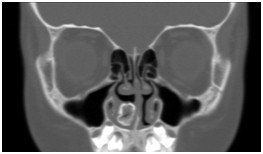

鼻窦(病例-异物):